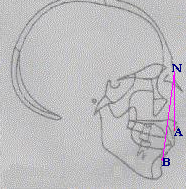

Arcos cigomaticos verticales; inclinación de incisivos superiores; barbilla en retroceso; ángulo escarpado de la mandíbula.; ANB aumentado ; Prognatismo maxillar.